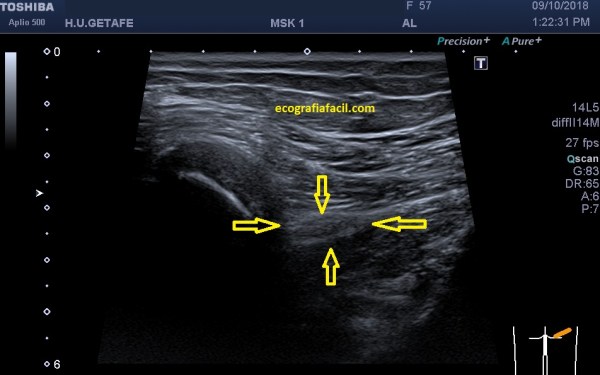

Los Tumores Neurogénicos (T.N.) son tumores de los Nervios, donde puede aparecer una lesión hipoecogénica y heterogéneaque antes y después de la lesión tienen un afilamiento (flechas amarillas) que se corresponde con la parte del Nervio no afectada y se continúa con el Nervio ecográficamente normal. Este hallazgo ecográfico es vital y además es diágnostico para el Radiólogo, en la mayoría de las ocasiones.